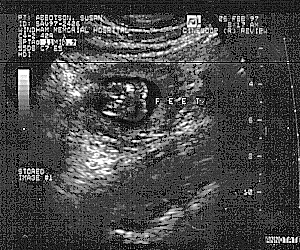

And take a peek at our newest member. A Humu in vitro! #1#2#3#4

As of July 17th, she's a Humu ex-vitro.